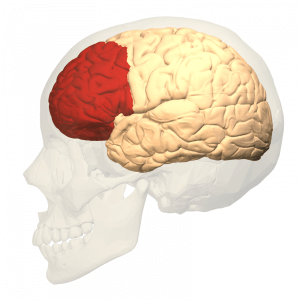

Dette er konsekvensen af en hjerneskade, hovedsagelig subkortikal. Lidelsen kan medføre en følelse af tabt identitet, eftersom den berørte patient ikke kan lade være med at tale med en anden accent, og fordi det sker så pludseligt.

Blandt hovedårsagerne er cerebrovaskulære ulykker og kraniocerebrale traumer, som påvirker områder, der er relateret til sprog og udtrykkelse. Derudover er der andre patologier som multipel sklerose, hjernetumorer og anæstesi.

Dette er konsekvensen af en hjerneskade, hovedsagelig subkortikal. Lidelsen kan medføre en følelse af tabt identitet, eftersom den berørte patient ikke kan lade være med at tale med en anden accent, og fordi det sker så pludseligt.

Blandt hovedårsagerne er cerebrovaskulære ulykker og kraniocerebrale traumer, som påvirker områder, der er relateret til sprog og udtrykkelse. Derudover er der andre patologier som multipel sklerose, hjernetumorer og anæstesi.